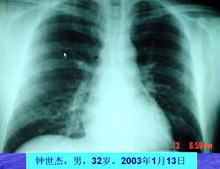

主持人:王丽(护士)是什么时候感染的? 王丽:我自己也不能明确说出自己的感染潜伏期有多长,但是我有明确的非典病人接触史,因为我在重症病房工作,3月13日我刚下班就发现自己双腿比较软,人有一种往下坠的感觉,开始以为是太疲劳导致的,回到宿舍量体温发现体温是38.4度,这时我赶紧就给科室打电话,然后拍了一个胸片后最终确诊为非典型肺炎。 张敏州:钟医生是我院第一个明确感染非典型肺炎的病人,最开始并不知道是感染了非典型肺炎,和黄丽护士一样开始都有疲乏无力的症状。 林琳:来看看胸片的情况:黄发胜的胸片可以看到一大片的阴影,发生了实变,正常的肺泡是充满空气的,而现在黄发胜的胸片显示没有空气。钟医生的胸片可以看到肺叶有发炎的现象。非典型肺炎的发病与季节有很大的关系,春天是呼吸系统疾病的高发季节。